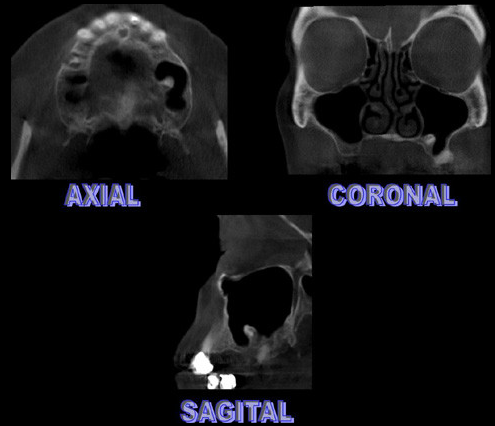

Paciente masculino 57años de edad, acude a la consulta para evaluación tomográfica previa a la colocación de implantes. En la radiografía panorámica observamos una imagen radiopaca proyectada en el antro del seno maxilar izquierdo. Se realiza estudio con tomografía volumétrica (Picasso E-WOO), se grafican cortes panorámicos, axiales, coronales y transaxiales que muestran claramente la imagen de densidad cálcica en el interior del seno maxilar izquierdo compatible con Antrolito.